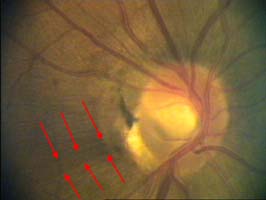

Tento terč má širokou cirkulární peripapilární atrofii, která opticky vytváří falešný dojem širokého neuroretinálního lemu, zvláště nasálně.

Na dolním pólu terče je patrný zálom vény, která zviditelňuje přítomnost i hloubku exkavace až k dolnímu okraji terče.

V nasálním horním kvadrantu terče vidíme obnažené cévy, které dříve probíhaly v lemu. Toto obnažení může být jedním z prvních příznaků glaukomové neuropathie.